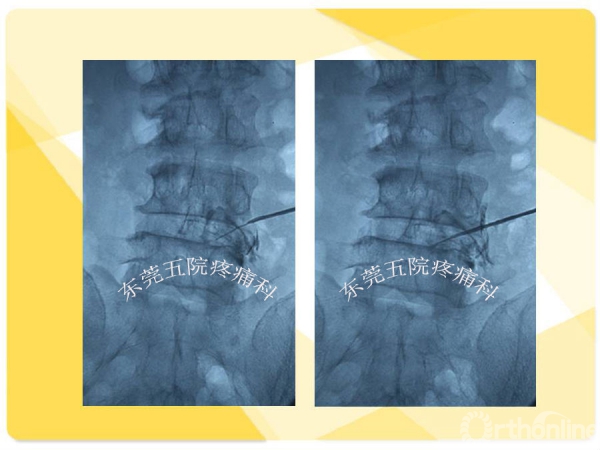

如何在椎间孔镜术前有效预防并发症的发生?如果不幸发生了该如何快速准确地处理?广东省东莞市第五人民医院疼痛科康健主任医师为大家分享了他的经验——